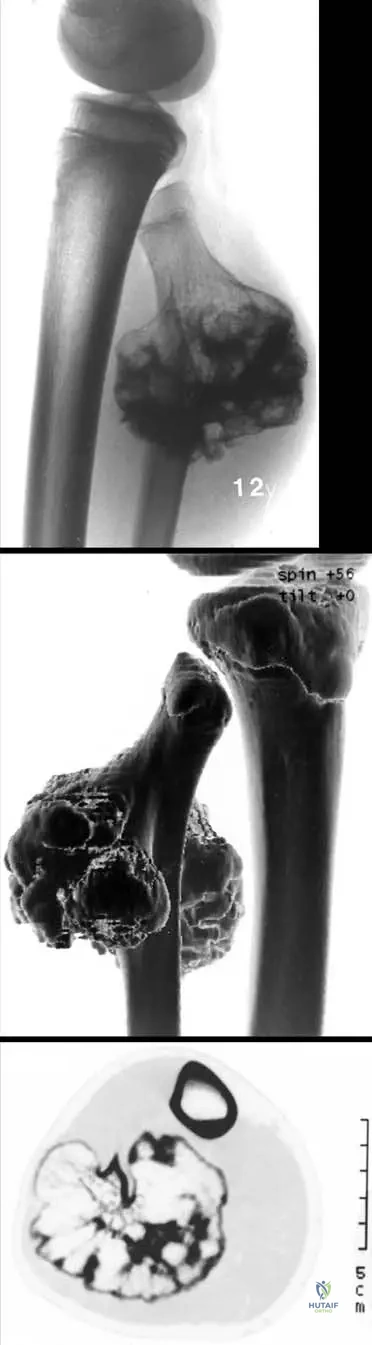

A biopsy is performed on a bony lesion from a 12-year-old boy. Histological examination reveals a cartilage cap undergoing enchondral ossification, with continuity of the marrow space with the underlying bone. This histological appearance most closely resembles which normal anatomical structure?

Rationale: Histologically, osteochondromas resemble physes (growth plates) due to their cartilage cap undergoing enchondral ossification. This is a key characteristic that explains their growth pattern and origin. Articular cartilage, epiphyseal bone, synovial membrane, and periosteum have distinct histological features that do not match the description.

A gross pathology specimen of an excised bony lesion from a 13-year-old patient reveals a stalked bony projection covered by a distinct, glistening cap. Upon sectioning, the marrow space within the projection is observed to be continuous with the marrow space of the parent bone. What is the composition of the glistening cap?

Rationale: Osteochondromas are characterized by a cartilage cap, which is composed of hyaline cartilage. This cap is responsible for the growth of the lesion through enchondral ossification, mimicking a physis. Fibrous tissue, adipose tissue, dense connective tissue, or immature woven bone are not the primary components of the cap.